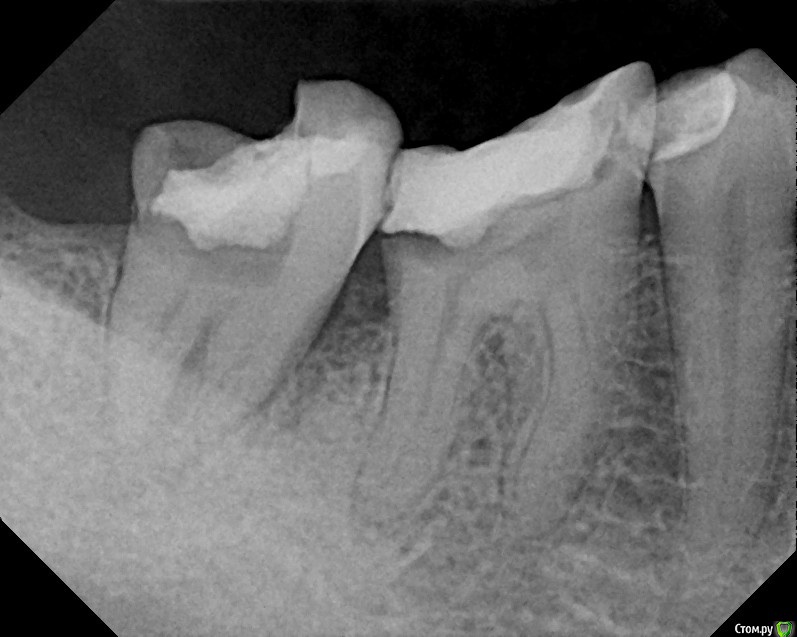

St616 Опубликовано 1 декабря, 2014 Поделиться Опубликовано 1 декабря, 2014 (изменено) Добрый день ! Прошу вас посмотрите пломбировку каналов метапексом После пломбировки 2 дня сильная боль при нажатии и вообще.Сегодня пятый день, зуб поднывает и еще качается. Дело в том что у меня грудной ребенок, я его кормлю и поэтому не хотелось может более сильных, но не безопасных средств. Нервы удаляли с анастезией без лекарств. Тк был предложен только мышьяк. А у меня ребенок га гв. Пломбировка каналов и окончатильная очистка уже через 7 дней в другой клинике, хотели гуттаперчей. Но тк зуб качался сделали метапексом, врач вроде хоть и молодой но оч грамотный. Меня волнует небольшое темное пятно в одном канале под пломбой, это что воздух там? Не из ха этого ди боль сохраняется, сейчас уже небольшая. Воач по снимку сказал, что всё хорошо, а боль из за того что метапекс вышел за пределы. Фото до и после Изменено 1 декабря, 2014 пользователем St616 Ссылка на комментарий